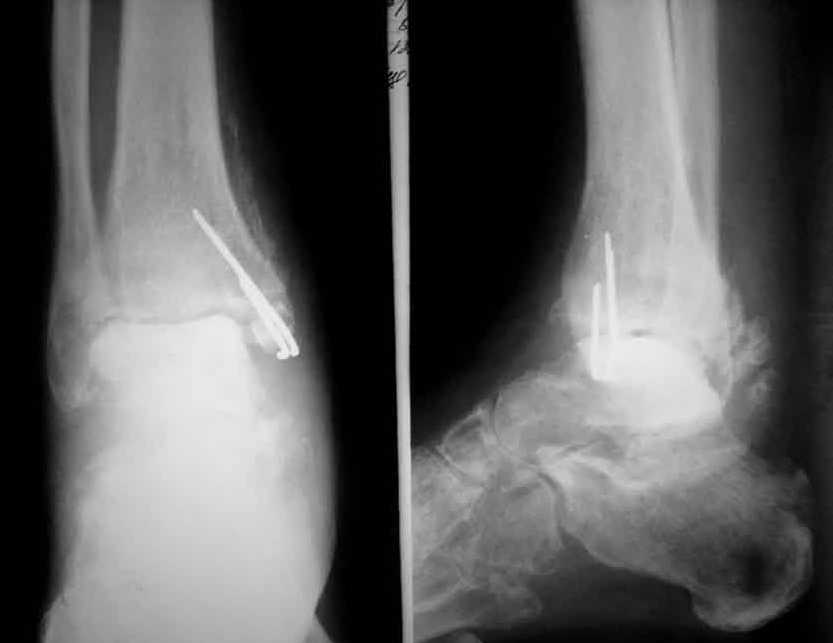

Коллеги! Хочется вынести на обсуждения ортофорума вопрос: - Как лечить асептический некроз таранной кости? Пациент Е., 52 года, Обратился в связи с болями при нагрузке в правом голеностопном суставе, ограничение движений.Травма 26.06.2004 в результате падения с высоты(прыгнул с лестницы). Лечился стационарно с диагнозом закрытый перелом правой таранной кости, обеих лодыжек со смещением. Выполнено оперативное лечение - остеосинтез лодыжки спицами, гипс. В сентябре 2004 спицы удалены. В сентябре 2004 острый правосторонний илеофеморальный тромбоз. Проведен курс консервативной терапии. В мае 2005 года больному проводился курс стационарного консервативного лечения по поводу посттравматического артроз правого голеностопного сустава. В ноябре 2005 года повторное ухудшение состояния, усиление болей повторный курс консервативного лечения в диагноз добавлен посттромбофлебитический синдром. ХВН 3А ст правой нижней конечности. В приложении R- до удаления спиц и последние R-граммы. C ув. Коробушкин Г.В.,РГМУ, Москва